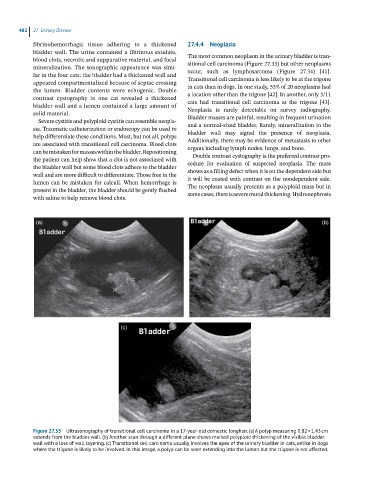

Figure 27.33 Ultrasonography of transitional cell carcinoma in a 17-year-old domestic longhair. (a) A polyp measuring 0.82 × 1.43 cm

extends from the bladder wall. (b) Another scan through a different plane shows marked polyploid thickening of the visible bladder

wall with a loss of wall layering. (c) Transitional cell carcinoma usually involves the apex of the urinary bladder in cats, unlike in dogs

where the trigone is likely to be involved. In this image, a polyp can be seen extending into the lumen but the trigone is not affected.